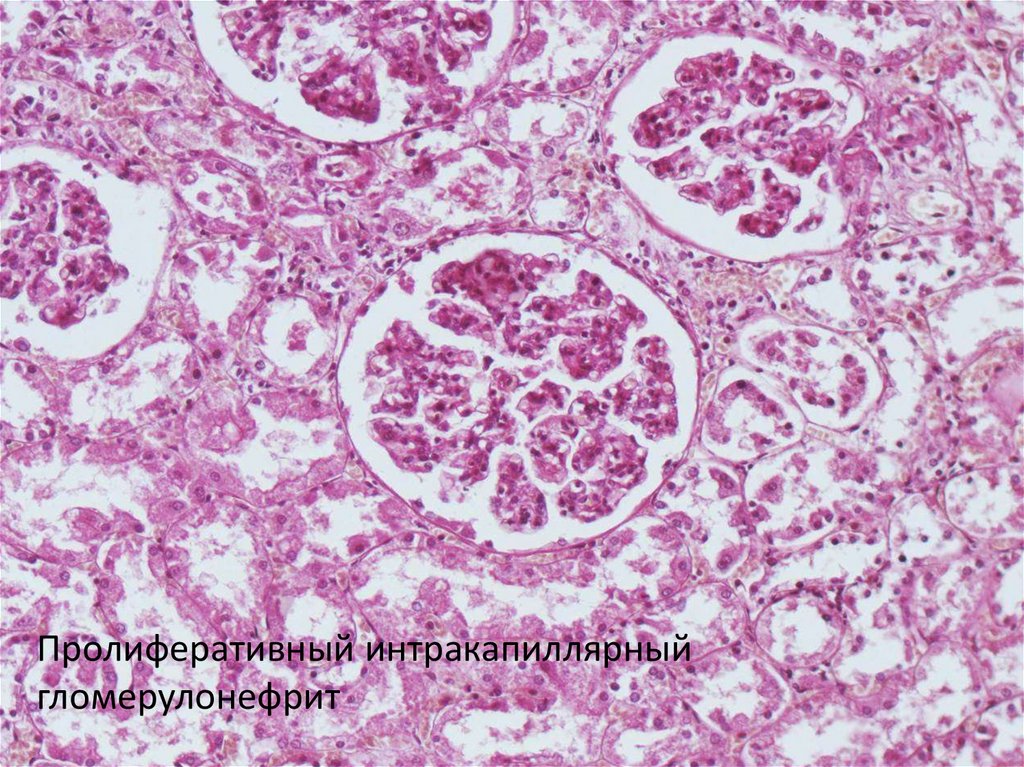

Пролиферативный интракапиллярный

гломерулонефрит